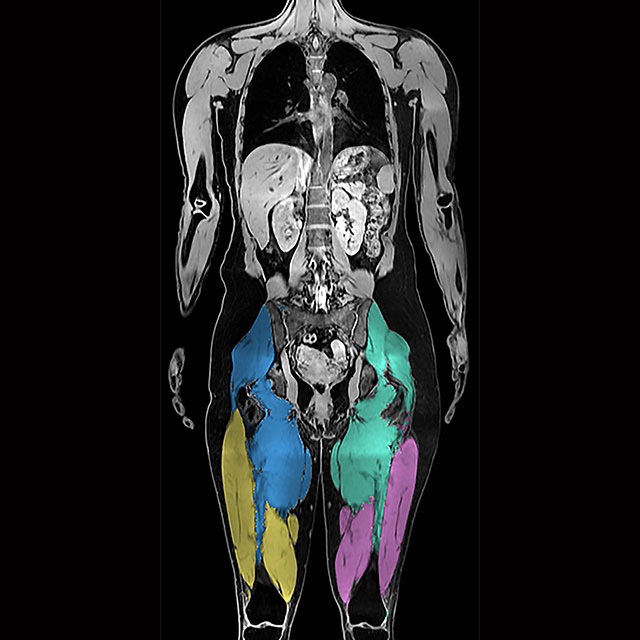

The AMRA® BCP Scan is a neck-to-knee MRI-based service using our validated protocols for creating an individualized Body Composition Profile (BCP). After we analyze the images, you receive an easy-to-interpret report containing precise body composition measurements with comparison to normative values.

- Evaluate the distribution of abdominal fat into visceral fat and subcutaneous fat

- Assess the health and volume of specific muscle groups

BCP Scan provides information to support weight loss management, measuring the volume of visceral fat, subcutaneous fat, and thigh muscles in relation to a reference population. It also measures the fat fraction in the liver and thigh muscles.

Muscle health impact

BCP Scan can be used to identify individuals with lower-than-expected muscle volume and elevated muscle fat content. Literature has shown that low muscle volume with high muscle fat content is predictive of mortality, linked to poor functional performance, and that muscle loss occurs during weight loss interventions 3,6,8,9,12. This information supports physicians in understanding muscle health during weight loss management.

Body composition measurements

- Visceral Fat

- Subcutaneous Fat

- Muscle Fat

- Muscle Volume